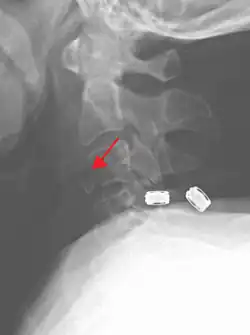

On CT scan or X-ray, a cervical fracture may be directly visualized. In addition, indirect signs of injury by the vertebral column are incongruities of the vertebral lines,[7] and/or increased thickness of the prevertebral space:[8]